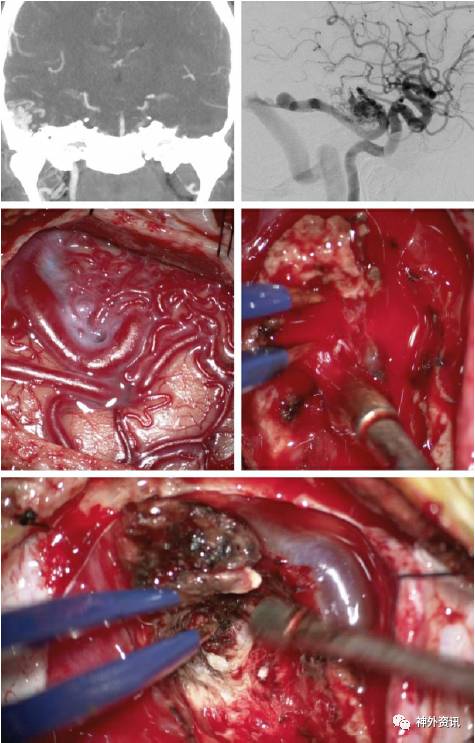

脑动静脉畸形破裂出血急症手术一例

图片尺寸1151x784